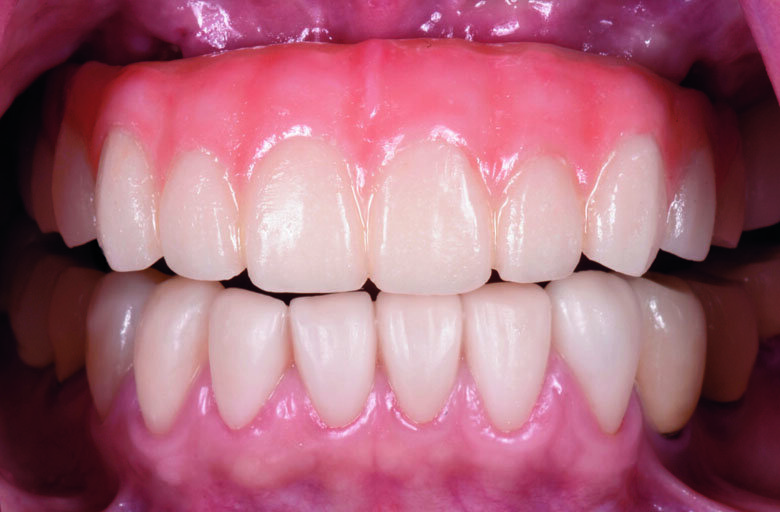

Fig. 24. Post-operative frontal view

Fig 25. Post-operative smile with provisional profile prosthesis

Fig . 26. Post-operative smile with provisional profile prosthesis

Fig 27. Post-operative smile with provisional profile prosthesis

Flapless guided-surgery with immediate loading protocol

The questionable teeth (13, 24 and 25) were extracted under local anaesthesia. The surgical guide was secured in place on the maxillary arch with two anchor pins. (Figs. 21) Flapless surgery was performed using guided tissue punch. Sequential drilling were made according to the manufacturer’s protocol. All implants were placed through the surgical template. All implants were torqued 35 NCm to ensure primary stability. The extraction socket were filled with small particle Xenograft (Bio-Oss, Geistlich) and covered with resorbable collagen plug (Collar plug, Zimmer Biomet). Straight and angle multi-unit abutments were seated and torqued 15 NCm on each implants (Fig. 23)

The existing provisional bridge was utilized for converting to a provisional screw-retained prosthesis. An immediate loading protocol was utilised2. Metal temporary abutments were connected on each implant. Provisional full arch bridge was perforated to match the position of the metal temporary abutments, placed in their correct position and OVD, relined with self-cure acrylic resin. All surfaces were fine-polished. A light-cure denture sealant (Palaseal, Kulzer) was applied on the intaglio surface. The provisional bridge was delivered to the patient’s mouth. (Figs. 23-27) Post-operative panoramic XRAY revealed that implants were placed according to the pre-operative planning (Fig. 22) Suture was removed after surgery 14 days. A final profile protheses3 will be fabricated after implant osseointegration.